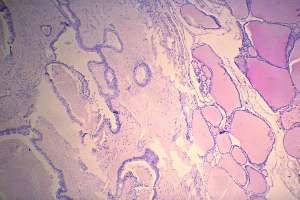

Histopathology: metastasis of a colon cancer to the thyroid.

The postoperative evaluation of the patient revealed metastasis to the lung and to the liver.